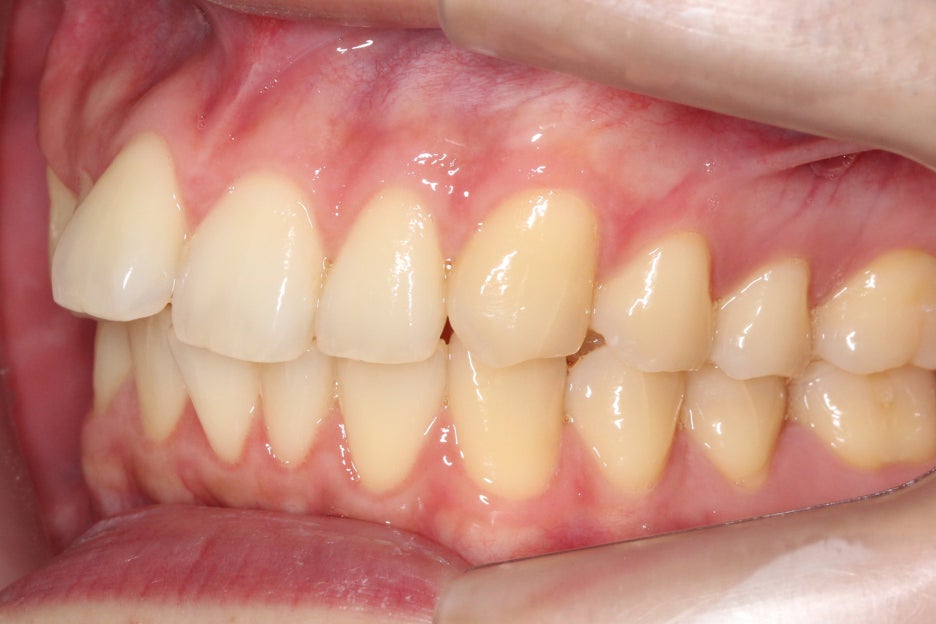

측면에서 overjet을 보면 중절치의

돌출 증상이 심한 모습으로 상악이

전방으로 뻐드러져 있어 입이 튀어나와 보이고

자꾸 입이 벌어지는 습관이 생길 수 있습니다.

이러한 경우 돌출된 앞니나 전치부를

교정하여 돌출감을 완화할 수 있어요.

2mm를 넘을 경우 돌출이 있다고 판단되기 때문에

치아를 교정하는 것이 좋습니다.

좌우의 교합평면을 보면 구치부의

교합은 비교적 양호한 편으로

부정교합 증상을 크게 나타나지 않는 모습이에요.